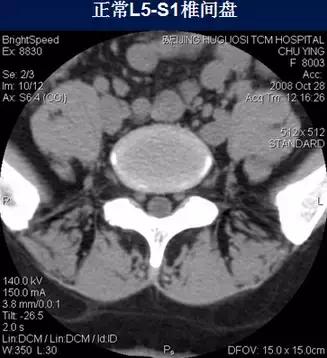

常规腰椎CT扫描L3-S1段,分为

(2)椎间盘层面(软组织窗):观察椎间盘、硬膜囊、神经根、韧带等软组织。